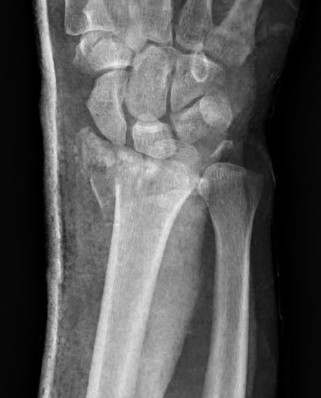

External Fixation + / - Supplemental K wires

Indications

Compound fractures

Severe unreconstructable injuries

Very osteoporotic bone

Technique

AO surgery wrist external fixation

Vumedi wrist external fixation video

Dorsal distal radius

- 2 x half pins 4mm

- proximally between EDC and ECRB / ECRL

- bare area of radius

Metacarpal

- 2 x half pins index or second metacarpal 3 mm

- distal and proximal metaphysis

- insert at 30 degrees to prevent transfixing extensor tendon

- flex MCP to 90 degrees with when placing distal pin to avoid extensor hood